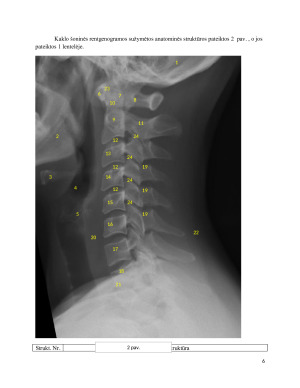

Stuburo kaklinės dalies šoninė rentgenograma